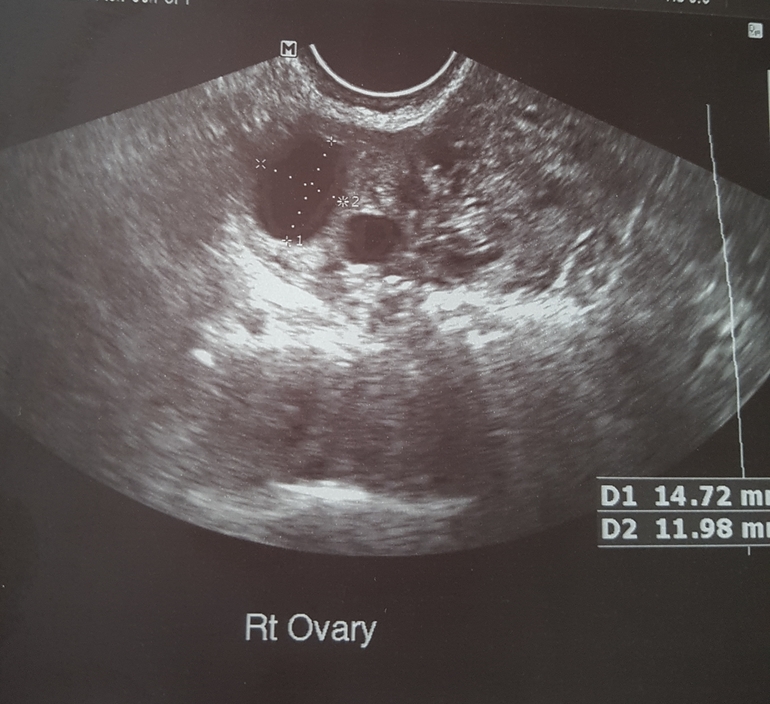

12дц. Сходила на узи для своего успокоения и вот, что имеем

ФолликулометрияСказали, все прекрасно: эндометрий почти 11 мм, в левом яичнике два дф (первый 26мм, второй 18мм), в правом яичнике (14мм и 12мм). Успокоили меня, всё работает, как у девушки молодой, сказала, что шов от кс отличный, и операцию мне сделали очень качественно. За это я тоже переживала. Запас яйцеклеток внушительный. Так что ждём весны и снова в бой! Надеюсь всё у нас получится 😊😊😊

Вы с такими фоликами можете близнецов зачать?? Или двойню? Смотрю у вас уже есть близняшки